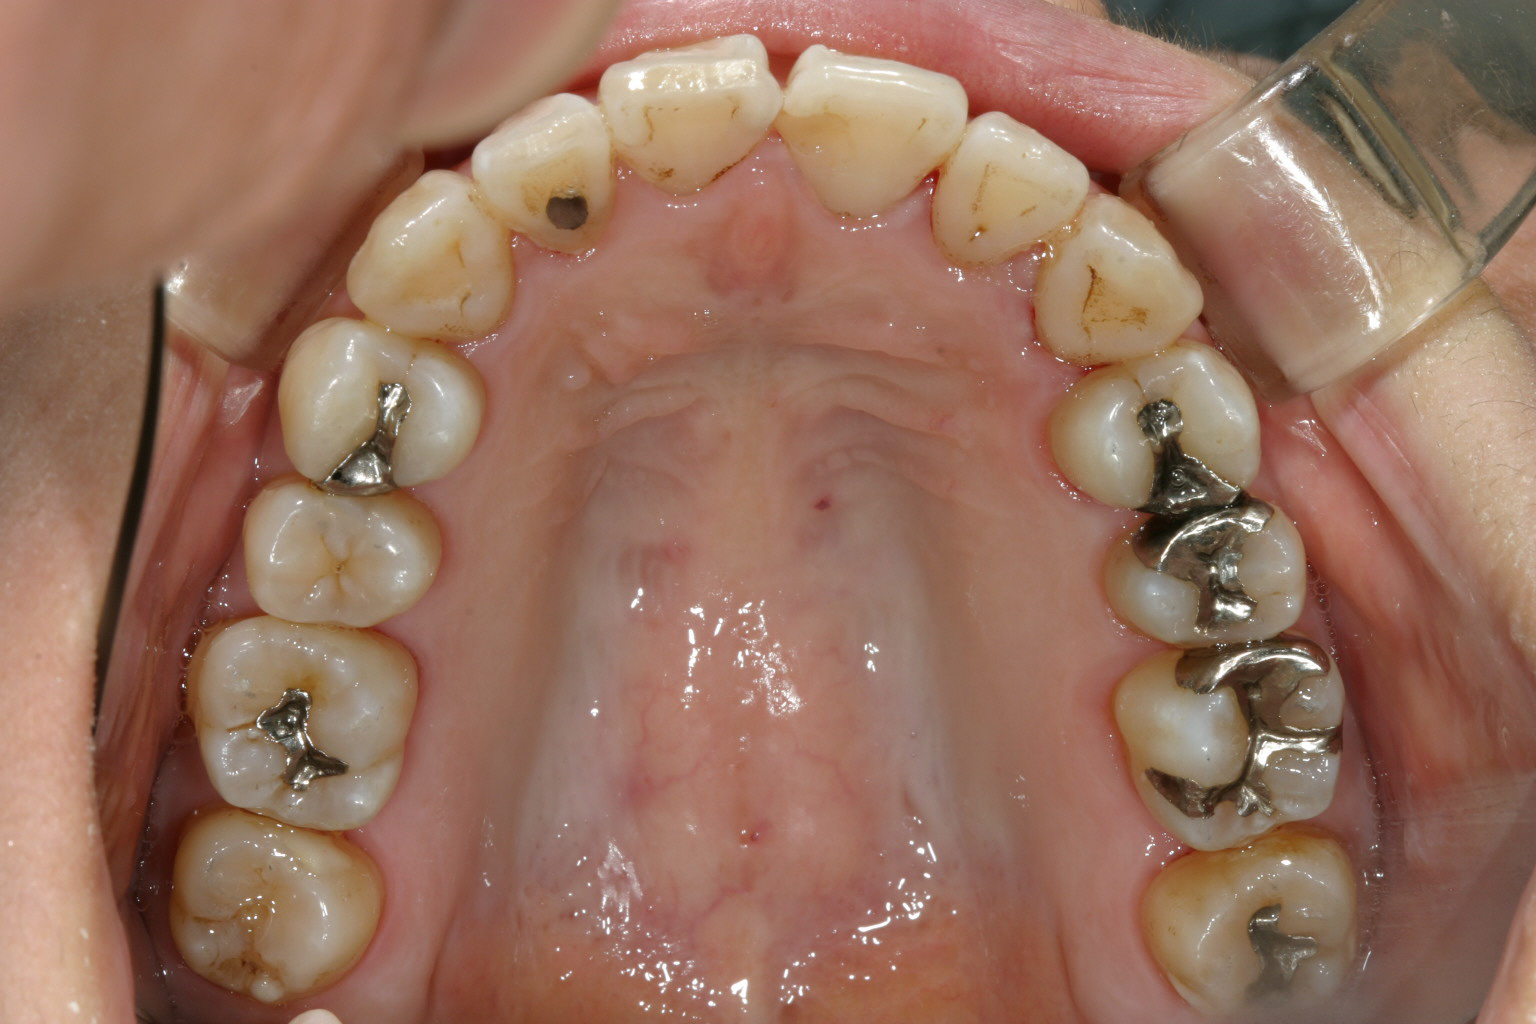

アーチの形状がV字になっている為、犬歯と犬歯の間が狭く前歯がガタガタになっています。

下顎もV字になっています。 又今日臼歯部が左右とも内方に傾斜しています。

綺麗に改善しました。

下顎も申し分有りません。